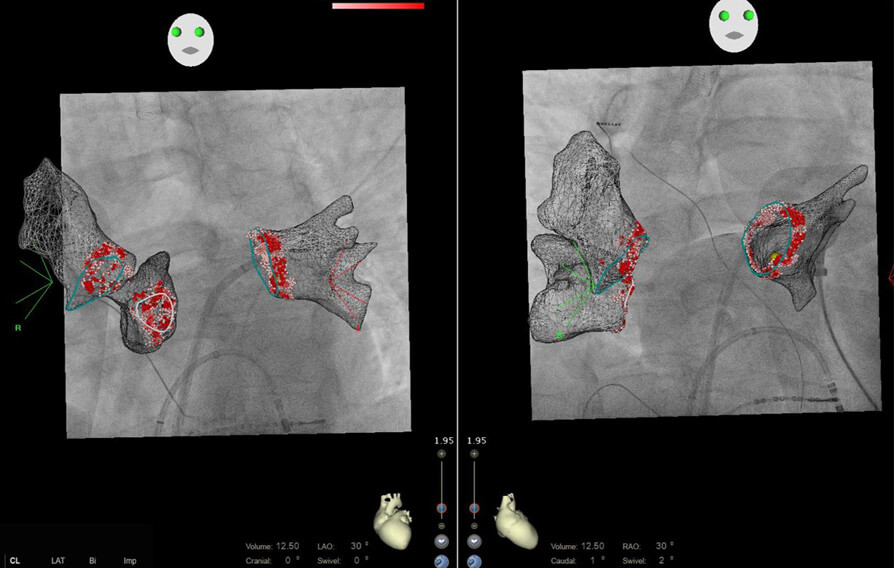

En muchos casos es asintomática y no requiere tratamiento antiarrítmico, pero en otros produce molestias y se debe tratar. Los fármacos antiarrítmicos suelen ser el tratamiento inicial, pero en pacientes que no toleren dicha medicación o en los que la arritmia persista a pesar de la misma, se puede realizar tratamiento mediante cateterismo, que tiene una tasa de eficacia entre el 60% y el 70%.”